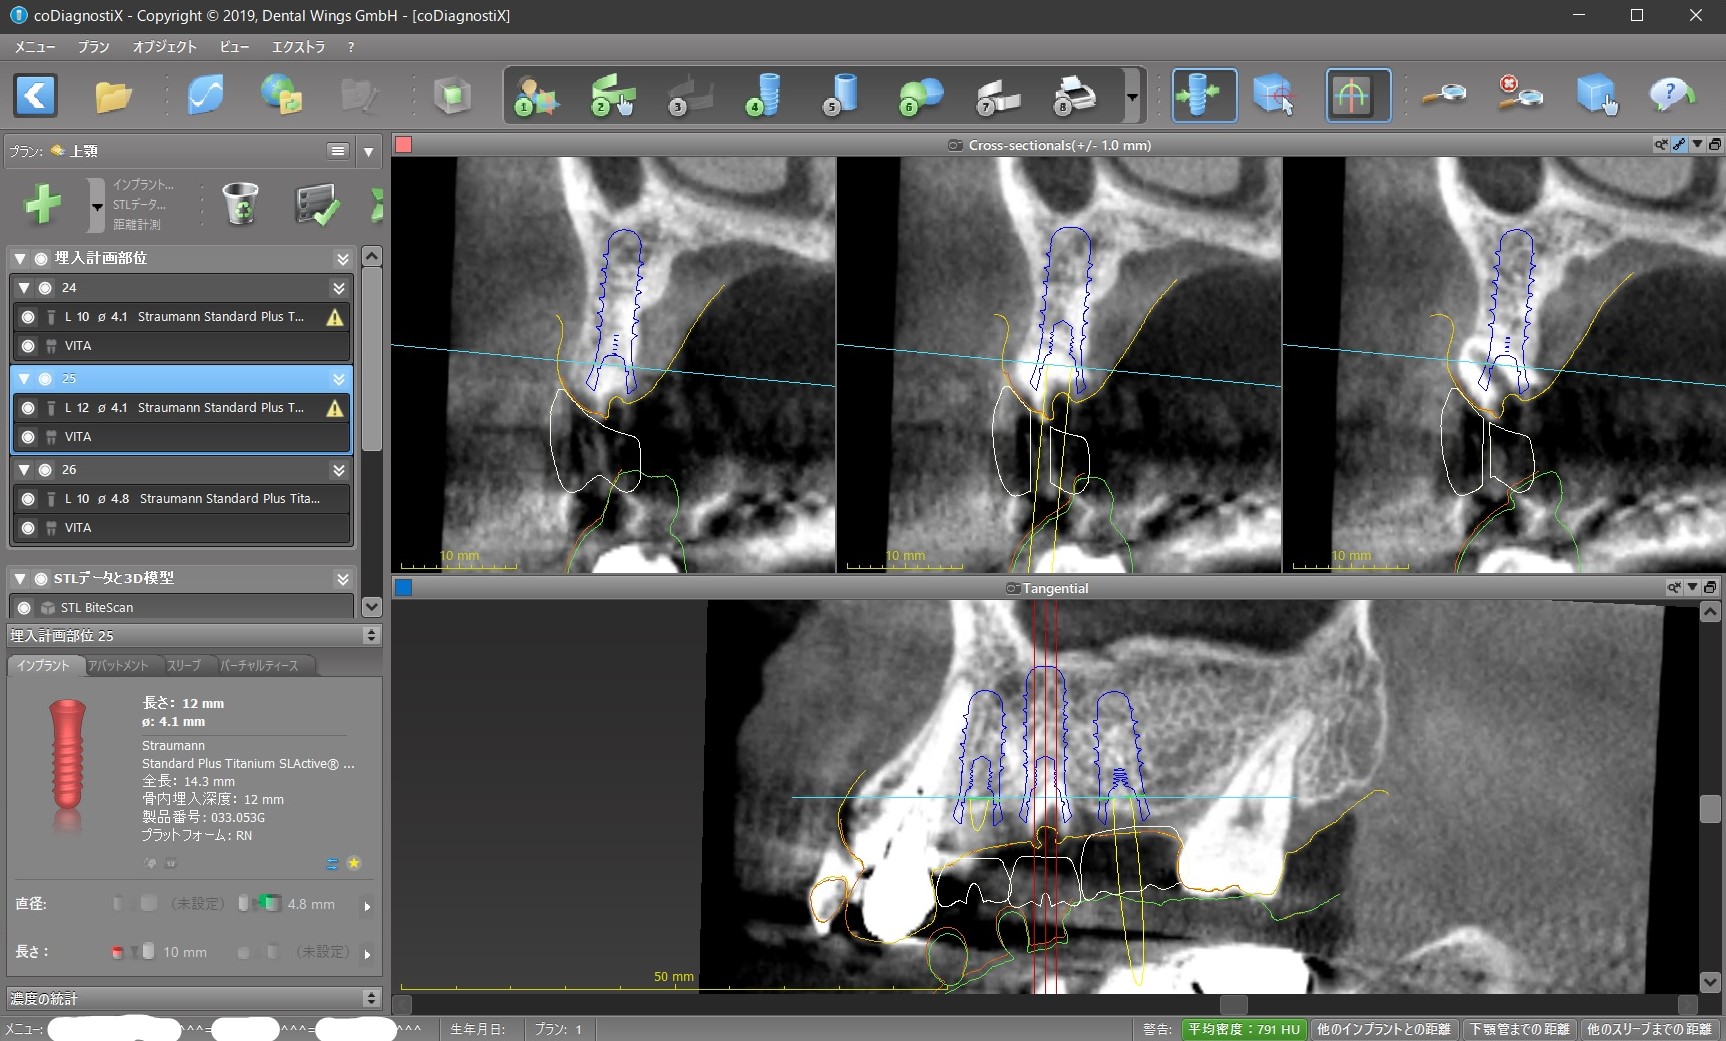

今回で言えば、インプラントを前から順に#24、#25、#26と呼ぶと

④ #25インプラント部位に歯の根が残っているので、これをインプラント手術の時に取り除くのと同時にそこに骨を増やす処置が必要になる。

今回、④の問題は対応が優しく、#25、#26部位はインプラントを入れる条件がかなり良いため、#24にはインプラントを入れずに#25と#26にだけインプラントを入れて、それを土台としたインプラントブリッジの設計にして、#24が下と咬まないことはご了承して頂くか矯正治療をするか相談するということになります。

そして方針が決まれば、コンピューター上でシュミレーションした位置に正確にインプラントが入れられる「サージカル・ガイド」を作成することになります。